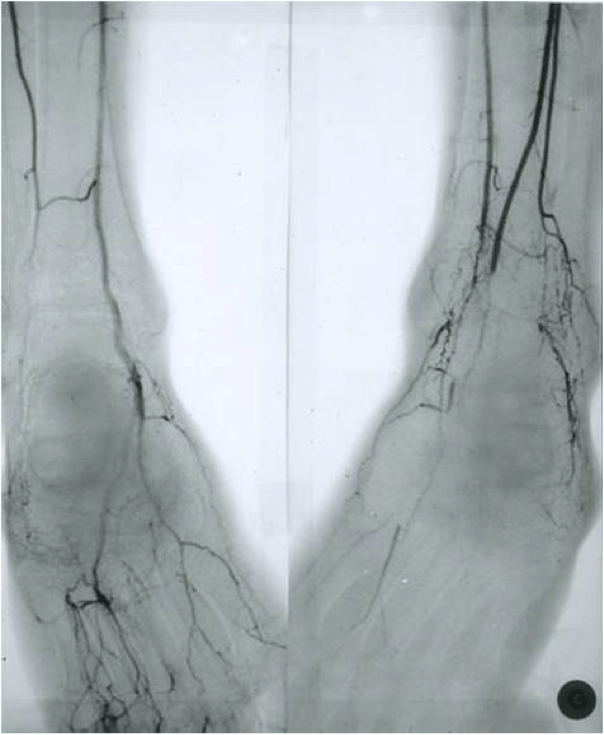

Observation n°3 : Un homme de 35 ans, admis aux urgences pour une ischémie critique des extrémités inférieures. Le malade décrivait une claudication intermittente des plantes des pieds puis des jambes depuis deux ans. Les pouls des pieds étaient abolis. Le reste de l’examen clinique était normal. Il n’avait ni diabète ni hypertension artérielle ni hyperlipidémie. La recherche d’un syndrome d’hypercoagulabilité était négative. L’écho-doppler artériel des membres inférieurs montrait une thrombose des trois axes jambiers au niveau de leurs parties terminales. L’artériographie des membres inférieurs montrait à droite une occlusion des artères tibiale postérieure au niveau de sa partie proximale et de l’artère fibulaire dans sa partie terminale avec une reprise par une circulation collatérale à partir de l’artère pédieuse et à gauche une occlusion des trois axes jambiers au niveau de leurs parties terminales avec aspect presque avasculaire du pied (figure 4). L’électrocardiogramme, l’échographie cardiaque et l’écho-Doppler pulsé des troncs supra-aortiques et des membres supérieurs étaient normaux. La chirurgie était impossible du fait du mauvais état artériel distal. Malgré l’arrêt du cannabis et du tabac, une cure pendant quatre semaines de prostaglandine vasodilatatrice, des anticoagulants et les soins locaux, l’amputation de l’avant pied gauche était inévitable.

L’évaluation angiographique met en évidence des anomalies artérielles distales, le plus souvent bilatérales, se présentant sous la forme de sténoses segmentaires, lisses et effilées. Il semble que la collatéralité soit plus développée que dans l’artérite de Buerger [2].